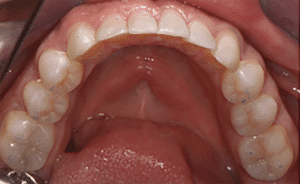

Mme AB vient en consultation pour deux raisons. La première est une douleur intense à chaque fois qu’elle boit ou mange froid. La deuxième est l’apparence de son sourire. Elle trouve que ses dents ont « raccourci » et qu’elles « s’effritent ». C’est devenu un complexe handicapant. À L’examen clinique on observe (Fig.1a, b, c, d, e) une usure vestibulaire de toutes les dents : plus prononcée au maxillaire et assez légère sur les incisives mandibulaires, une classe III canine et molaire droite, une classe I canine et molaire gauche avec une légère déviation des milieux et une usure importante des faces palatines du bloc IC maxillaire ainsi que des faces occlusales de 16 et 26. On constate aussi que les faces occlusales des autres dents sont moins touchées en apparence. On observe que les amalgames de 36 et 48 sont en relief par rapport à la dent support. Il est raisonnable de supposer qu’à l’origine ils devaient obturer une cavité et donc être à l’intérieur de la dent. Ceci témoigne donc aussi d’une forte usure sur 36 et 46. On observe enfin que les courbes de Spee sont complètement plates.

Fig.1a, b, c, d, e : Examen clinique.

Fig.1b.

Fig.1c.

Fig.1d.

Fig.1e.